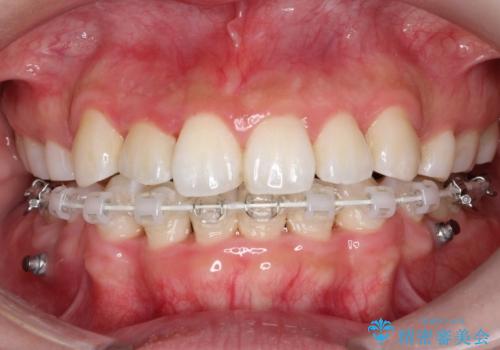

八重歯を改善!美しい口元を実現するハーフリンガル矯正

- 矯正装置

- ハーフリンガル

- 前歯のガタツキと口元のコンプレックスを解消するために来院されました。

ハーフリンガルワイヤー矯正で治療を開始しました。

ハーフリンガル矯正は、見た目を気にせずに矯正治療ができる方法です。この治療法は、八重歯や前歯のガタツキを効果的に改善します。特徴として、ワイヤーが上の歯の裏側に装着されるため、装置が外から見えません。これにより、治療中も自然な笑顔を保ちながら安心して治療を続けることができます。歯並びの悩みを持つ方にとって、非常に魅力的な選択肢です。